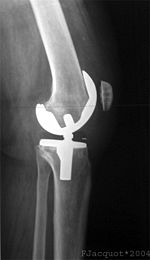

جراحة إستبدال الركبة يمكن أن تكون إستبدالا جزئياً أو إستبدال الركبة بالكامل.[2] في الإستبدال بصفة عامة تتكون من جراحة استبدال الأسطح المريضة أو التالفة للركبة بأجزاء معدنية أو بلاستيكية على شكل مكونات تسمح باستمرار حركة الركبة.

لاحقا، يتم تعديل أسطح المفصل بحيث تستطيع احتواء المفصل الاصطناعي المركب من البلاستيك والمعدن. يتم الصاق المفصل الاصطناعي بعظمة الفخذ، الساق والرضفة، بواسطة مادة ملاطية أو مادة أخرى، تستعمل كمادة لاصقة فسيولوجية. من ثم، يتم تثبيت المفصل الاصطناعي إلى عضلات الركبة والأربطة الداعمة للمفصل، من أجل الحصول على أداء حركي في المفصل بشكل مماثل للوضع الطبيعي. يتكون الجزء الملتصق بعظمة الفخذ من معدن صلب وأملس، والذي يستطيع تحمل أوزان ثقيلة. يتم تغطية المفصل بضمادة مرنة.